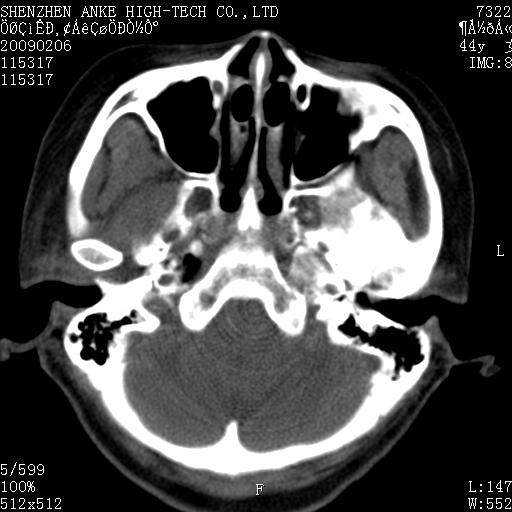

标题: CT17977:女,44岁,右侧颌部包块1年,右侧面瘫2月。 [打印本页]

患者:女,44岁,右侧颌部包块1年,右侧面瘫2月。

考虑右侧腮腺混合瘤可能性大

考虑右侧腮腺混合瘤。

考虑右侧腮腺混合瘤。年轮样伪影考虑机器问题!

考虑右侧腮腺混合瘤;不排除腮腺癌。

右侧腮腺肿瘤,良恶性难定。